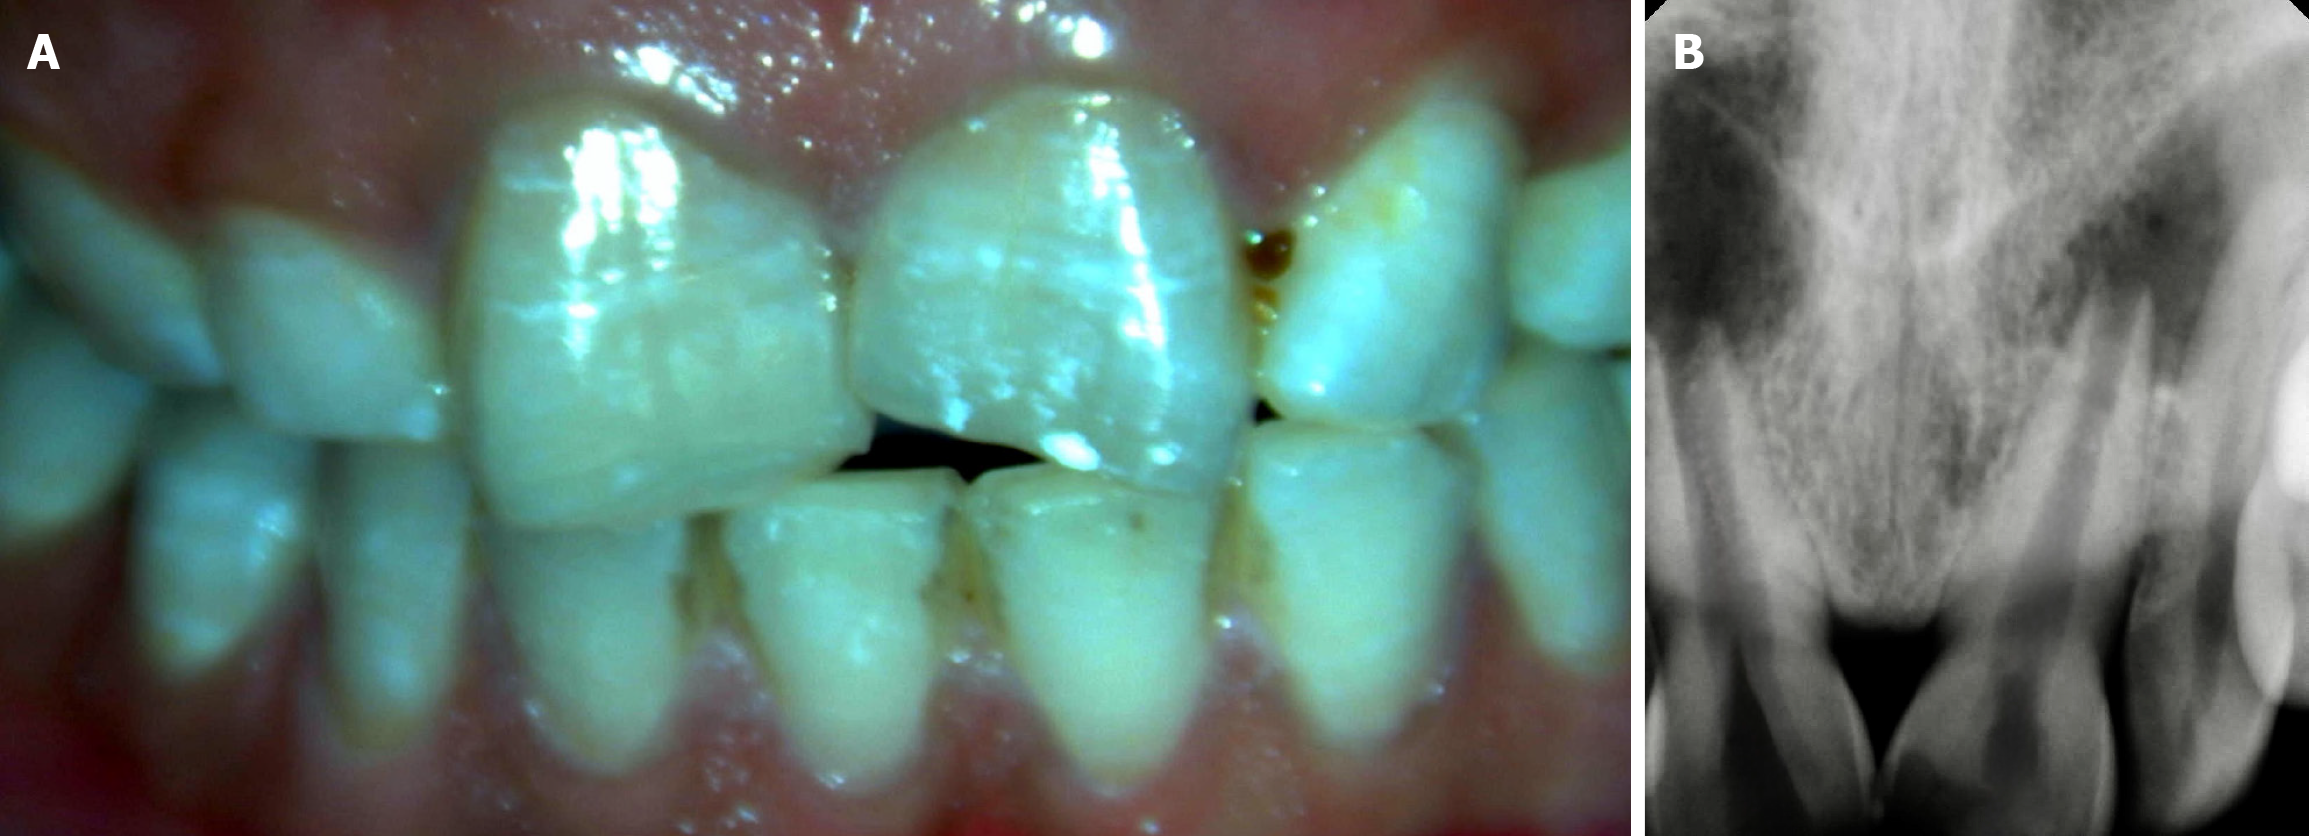

Figure 1 Clinical and radiographic examination.

A: Clinical image wrt 11 and 21; B: Radiograph wrt 11 and 21.